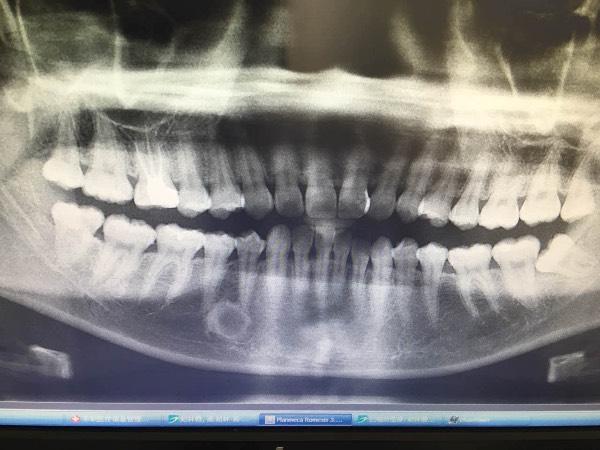

请专家帮忙看下牙齿x光图,右下的智齿是否需要拔除?

让你们看看什么是牙齿矫正,整一送一,拔牙送下巴!